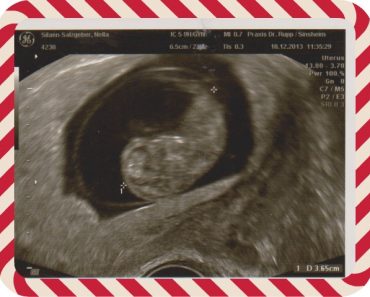

4. Pemeriksaan USG (diruangan dokter dilakukan oleh dokternya)

• Pemeriksaan 1 dan 2 dilakukan menggunakan alat yang dimasukkan melalui kelamin. Rasanya tidak nyaman pas dimasukkan alat tersebut. Saya tidak tahu nama alatnya. Bentuknya mirip bohlam lampu yang panjang yang warna putih susu. Alatnya panjang, makanya aneh (sakit) pas masuk. Setelah alatnya masuk, bisa lihat janinnya di monitor.

• Pemeriksaan ke 3 & 4 melalui bagian atas perut. Perut diolesi gel lalu alat usgnya digerak-gerakkan di atas perut kelihatan di dedeknya 🙂 .

18.12.2013 pada pemeriksaan ke 2 ukuran janin 3 cm,65 (juga masih imutt) ; ukuran (panjang) rahimnya 6,5 cm.usia 12 minggu